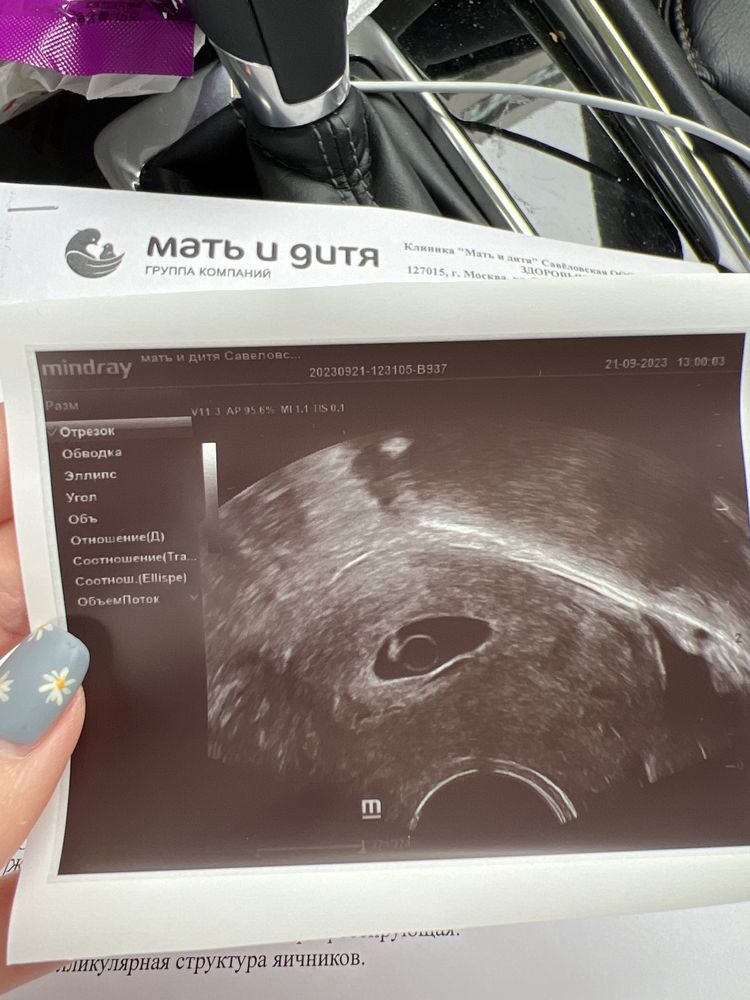

Я БЕРЕМЕННА !В четверг ездила на прием к ре , по узи все хорошо , только немного большой желточный мешочек . В норму вписывается 5,2мм ( норма вроде как до 6мм) но все равно переживаешь, у кого-то может было так ?Сердце включили прослушать 💗